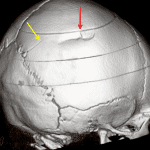

- Acute slightly depressed right parietal bone fracture with a nondisplaced fracture component versus accessory parietal suture extending posteriorly into the lambdoid suture

- Small parietal scalp hematoma

Acute right parietal calvarial fracture with 2 mm depression. A nondisplaced fracture component versus accessory parietal suture extends posteriorly into the lambdoid suture without sutural diastasis.

Small parietal scalp hematoma.